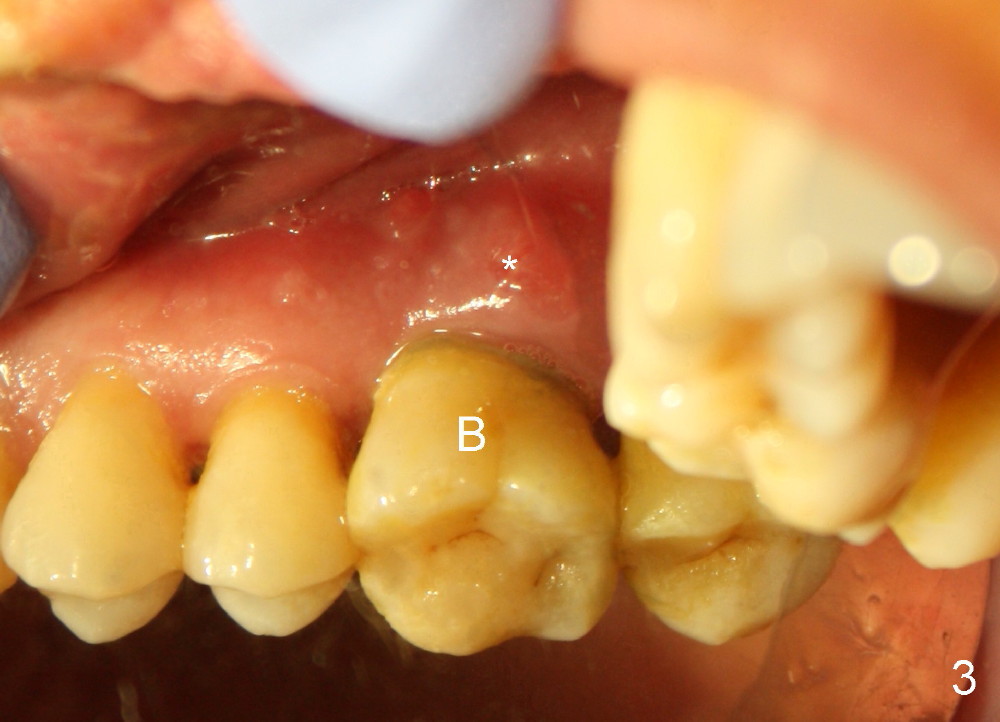

The upper right 1st molar of a 48-year-old man has severe perio endo disease (Fig.1 #3); the bone height for immediate implant (Fig.2) is about 3.5 mm (Fig.1 vertical line). There is a buccal (Fig.3 B) abscess (*); the palatal (Fig.4 P) root is exposed. After extraction, the socket available for immediate implant (Fig.5,6 S) is buccal (without septum), whereas the apex of the palatal root is far away from the main socket. In fact there is an advantage: the socket is smaller. Osteotomy is created in the main socket as palatal as possible, using osteotomes, reamers and taps (Fig.7 T). The sinus floor is lifted (Fig.7 ^). When 7x17 mm implant is placed (Fig.8 I), the insertion torque is >60 Ncm. The remaining socket (Fig.8 *) is to be packed with mixture of autogenous bone, allograft and synthetic bone (Osteogen) (Fig.9,10 <). Immediate insertion of an abutment (Fig.8-10 A) helps retain perio dressing (Fig.11,12). No collagen membrane is used in this case to cover the bone graft before placement of perio dressing. Postop the patient cannot tolerate oral Amoxicillin because of stomach upset. The dose is reduced. Two weeks postop, the perio dressing is stable, but discolors (Fig.13). When the dressing is removed, the buccal bone graft is exposed, which is not abnormal. What is unusual is discoloration (Fig.14). The significance of the latter is not revealed until 3 months postop when the patient remains asymptomatic, but there is an apical fistula (Fig.15 <). There is a communication between the fistula and the buccal sulcus of the implant: water passing freely. Based on the position of the buccal plate of the neighboring teeth (*), the buccal plate of the implant should be lost, which is consistent with finding of PA (Fig.16, as compared to Fig.8). Guided bone regeneration seems necessary.